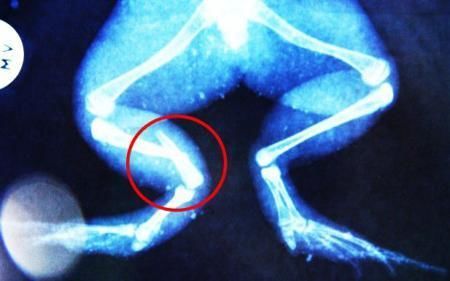

環(huán)球網(wǎng)4月2日?qǐng)?bào)道 據(jù)《每日郵報(bào)》報(bào)道,上個(gè)月,南非大牛蛙布魯萊的右小腿被鄰居家的一只狗咬到,導(dǎo)致粉碎性骨折,現(xiàn)在經(jīng)過(guò)2個(gè)小時(shí)的手術(shù),它的斷腿已經(jīng)被接上,它也因此成為有史以來(lái)第一只通過(guò)外科手術(shù)用鋼針接上斷腿的青蛙。

野生生物專家安妮經(jīng)常為學(xué)校寫教材,她認(rèn)為這是人類第一次通過(guò)手術(shù)給一只青蛙接斷腿。在手術(shù)開始階段,獸醫(yī)把少量給狗用的麻醉藥注入到這只青蛙體內(nèi),讓它失去知覺。然后他在布魯萊的斷腿上切開一個(gè)小口,把一根小鋼針植入腿里。最后獸醫(yī)給它縫了9針,把切口縫合在一起。僅僅幾周后,布魯萊就能在安妮家附近活動(dòng)了。這只青蛙大約已有25歲,主要以嚙齒動(dòng)物、蛇和其他青蛙為食。布魯萊所屬的牛蛙種群正在不斷減小,目前只能在非洲南部的濕地里才能看到這種青蛙。